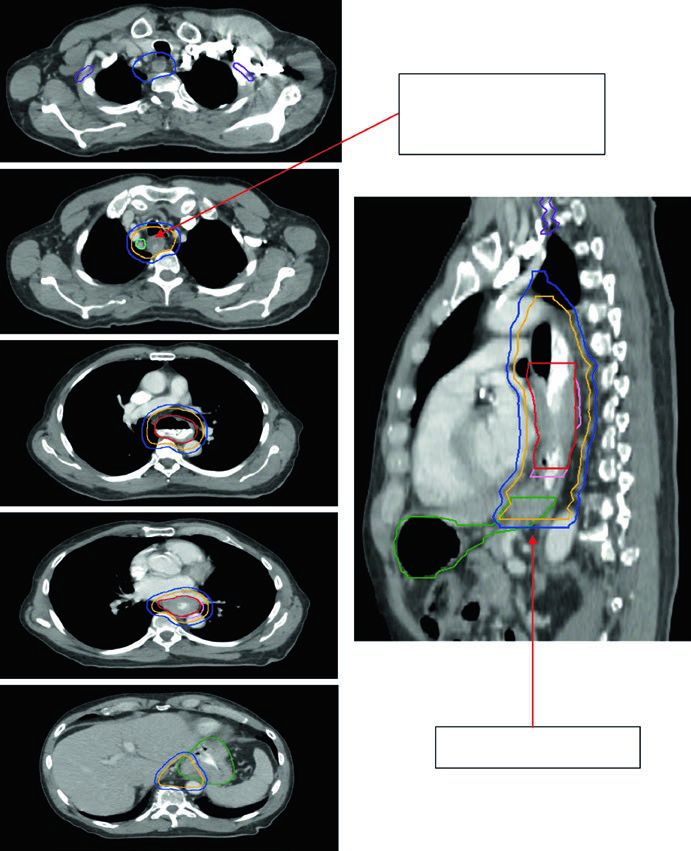

Caso 1: CEC Cervical/Torácico Superior — 69 anos

Paciente de 69 anos com CEC do esôfago cervical/torácico superior. O PET-CT revelou captação de FDG no tumor primário e linfonodos paratraqueais discretamente captantes. A EGD demonstrou massa ulcerada submucosa entre 15 e 23 cm dos incisivos. Os volumes delineados incluíram: plexo braquial (roxo), laringe (amarelo), GTV esofágico (vermelho), GTV nodal (verde), CTV (laranja), PTV 54 Gy (ciano) e PTV 60 Gy (azul escuro). O borda superior do campo supraclavicular foi posicionada na borda inferior da cartilagem cricoide, com cobertura nodal supraclavicular bilateral eletiva.